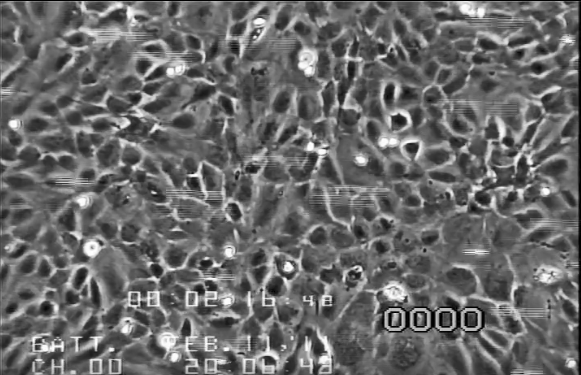

流体活细胞-活细胞成像

流体下的活细胞成像可以实时可视化剪切应力效应(例如,肌动蛋白应激纤维的形成)

HUVEC在20 dyn/cm2下培养的LifeAct-TagGFP2。图像分别以相差和荧光拍摄